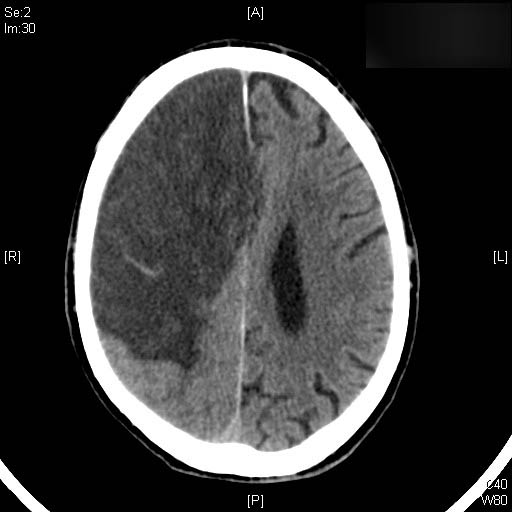

AVC amplio de territorio de A. cerebral media